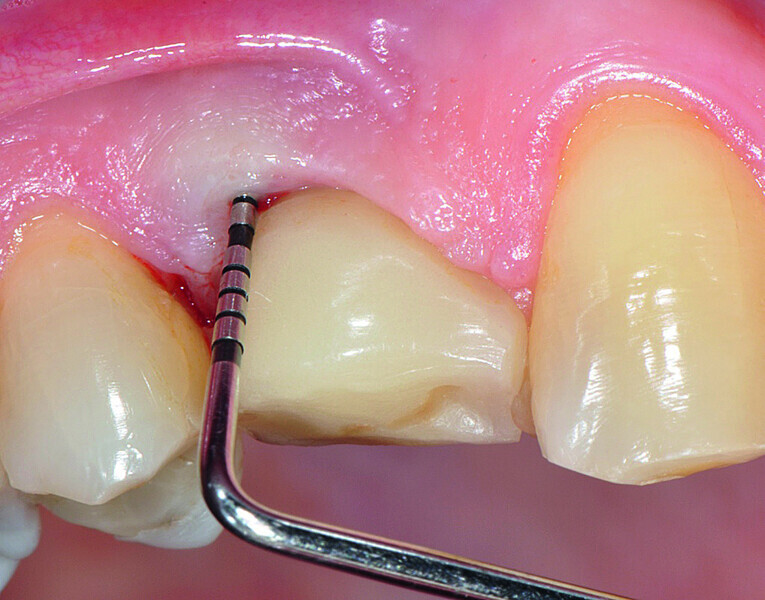

Fig. 1a: Implant in position #14 affected by peri-implantitis: periimplant probing a) with the prosthetic crown in situ and b) after prosthetic crown removal.

Fig. 1b: Implant in position #14 affected by peri-implantitis: periimplant probing a) with the prosthetic crown in situ and b) after prosthetic crown removal.